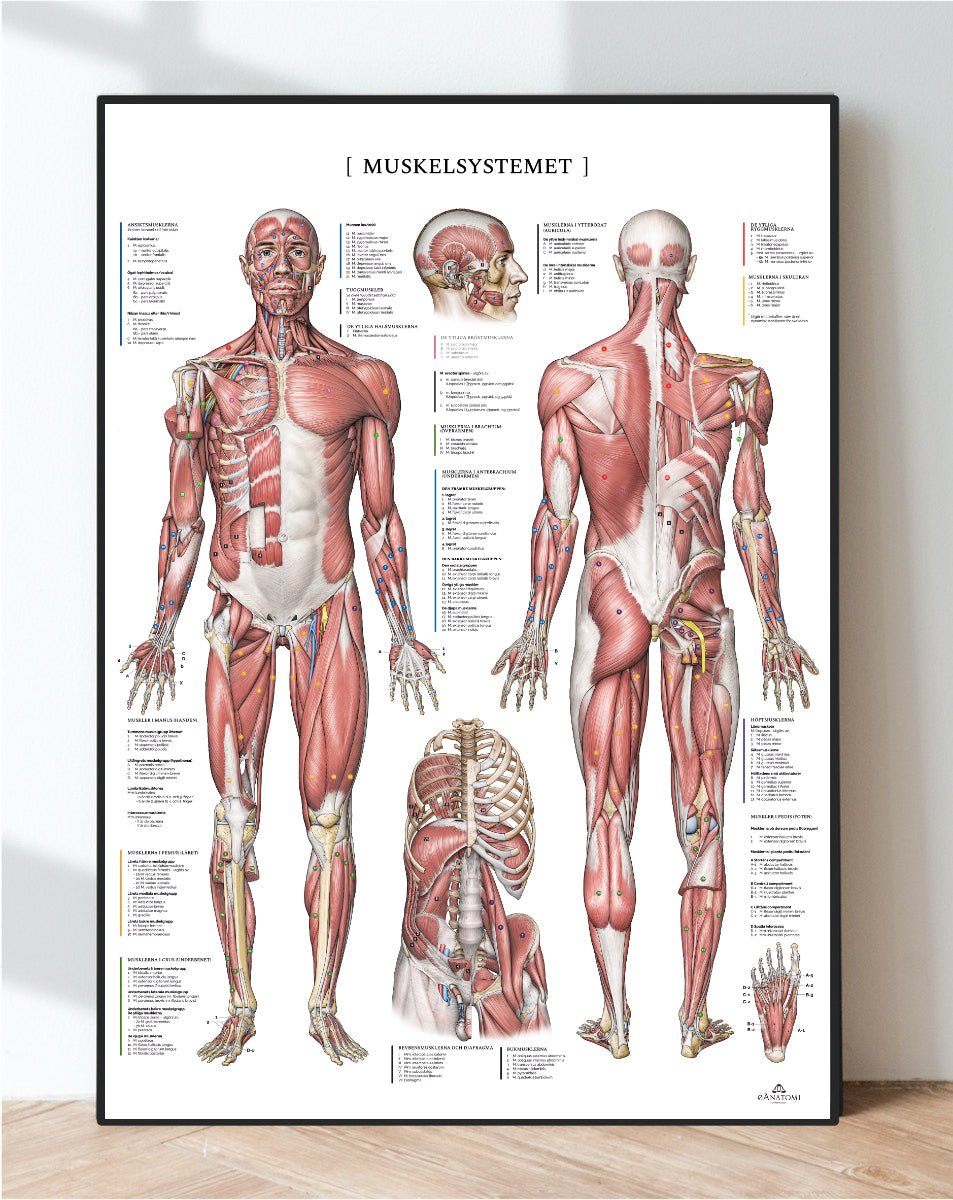

Vores anatomiske varesortiment